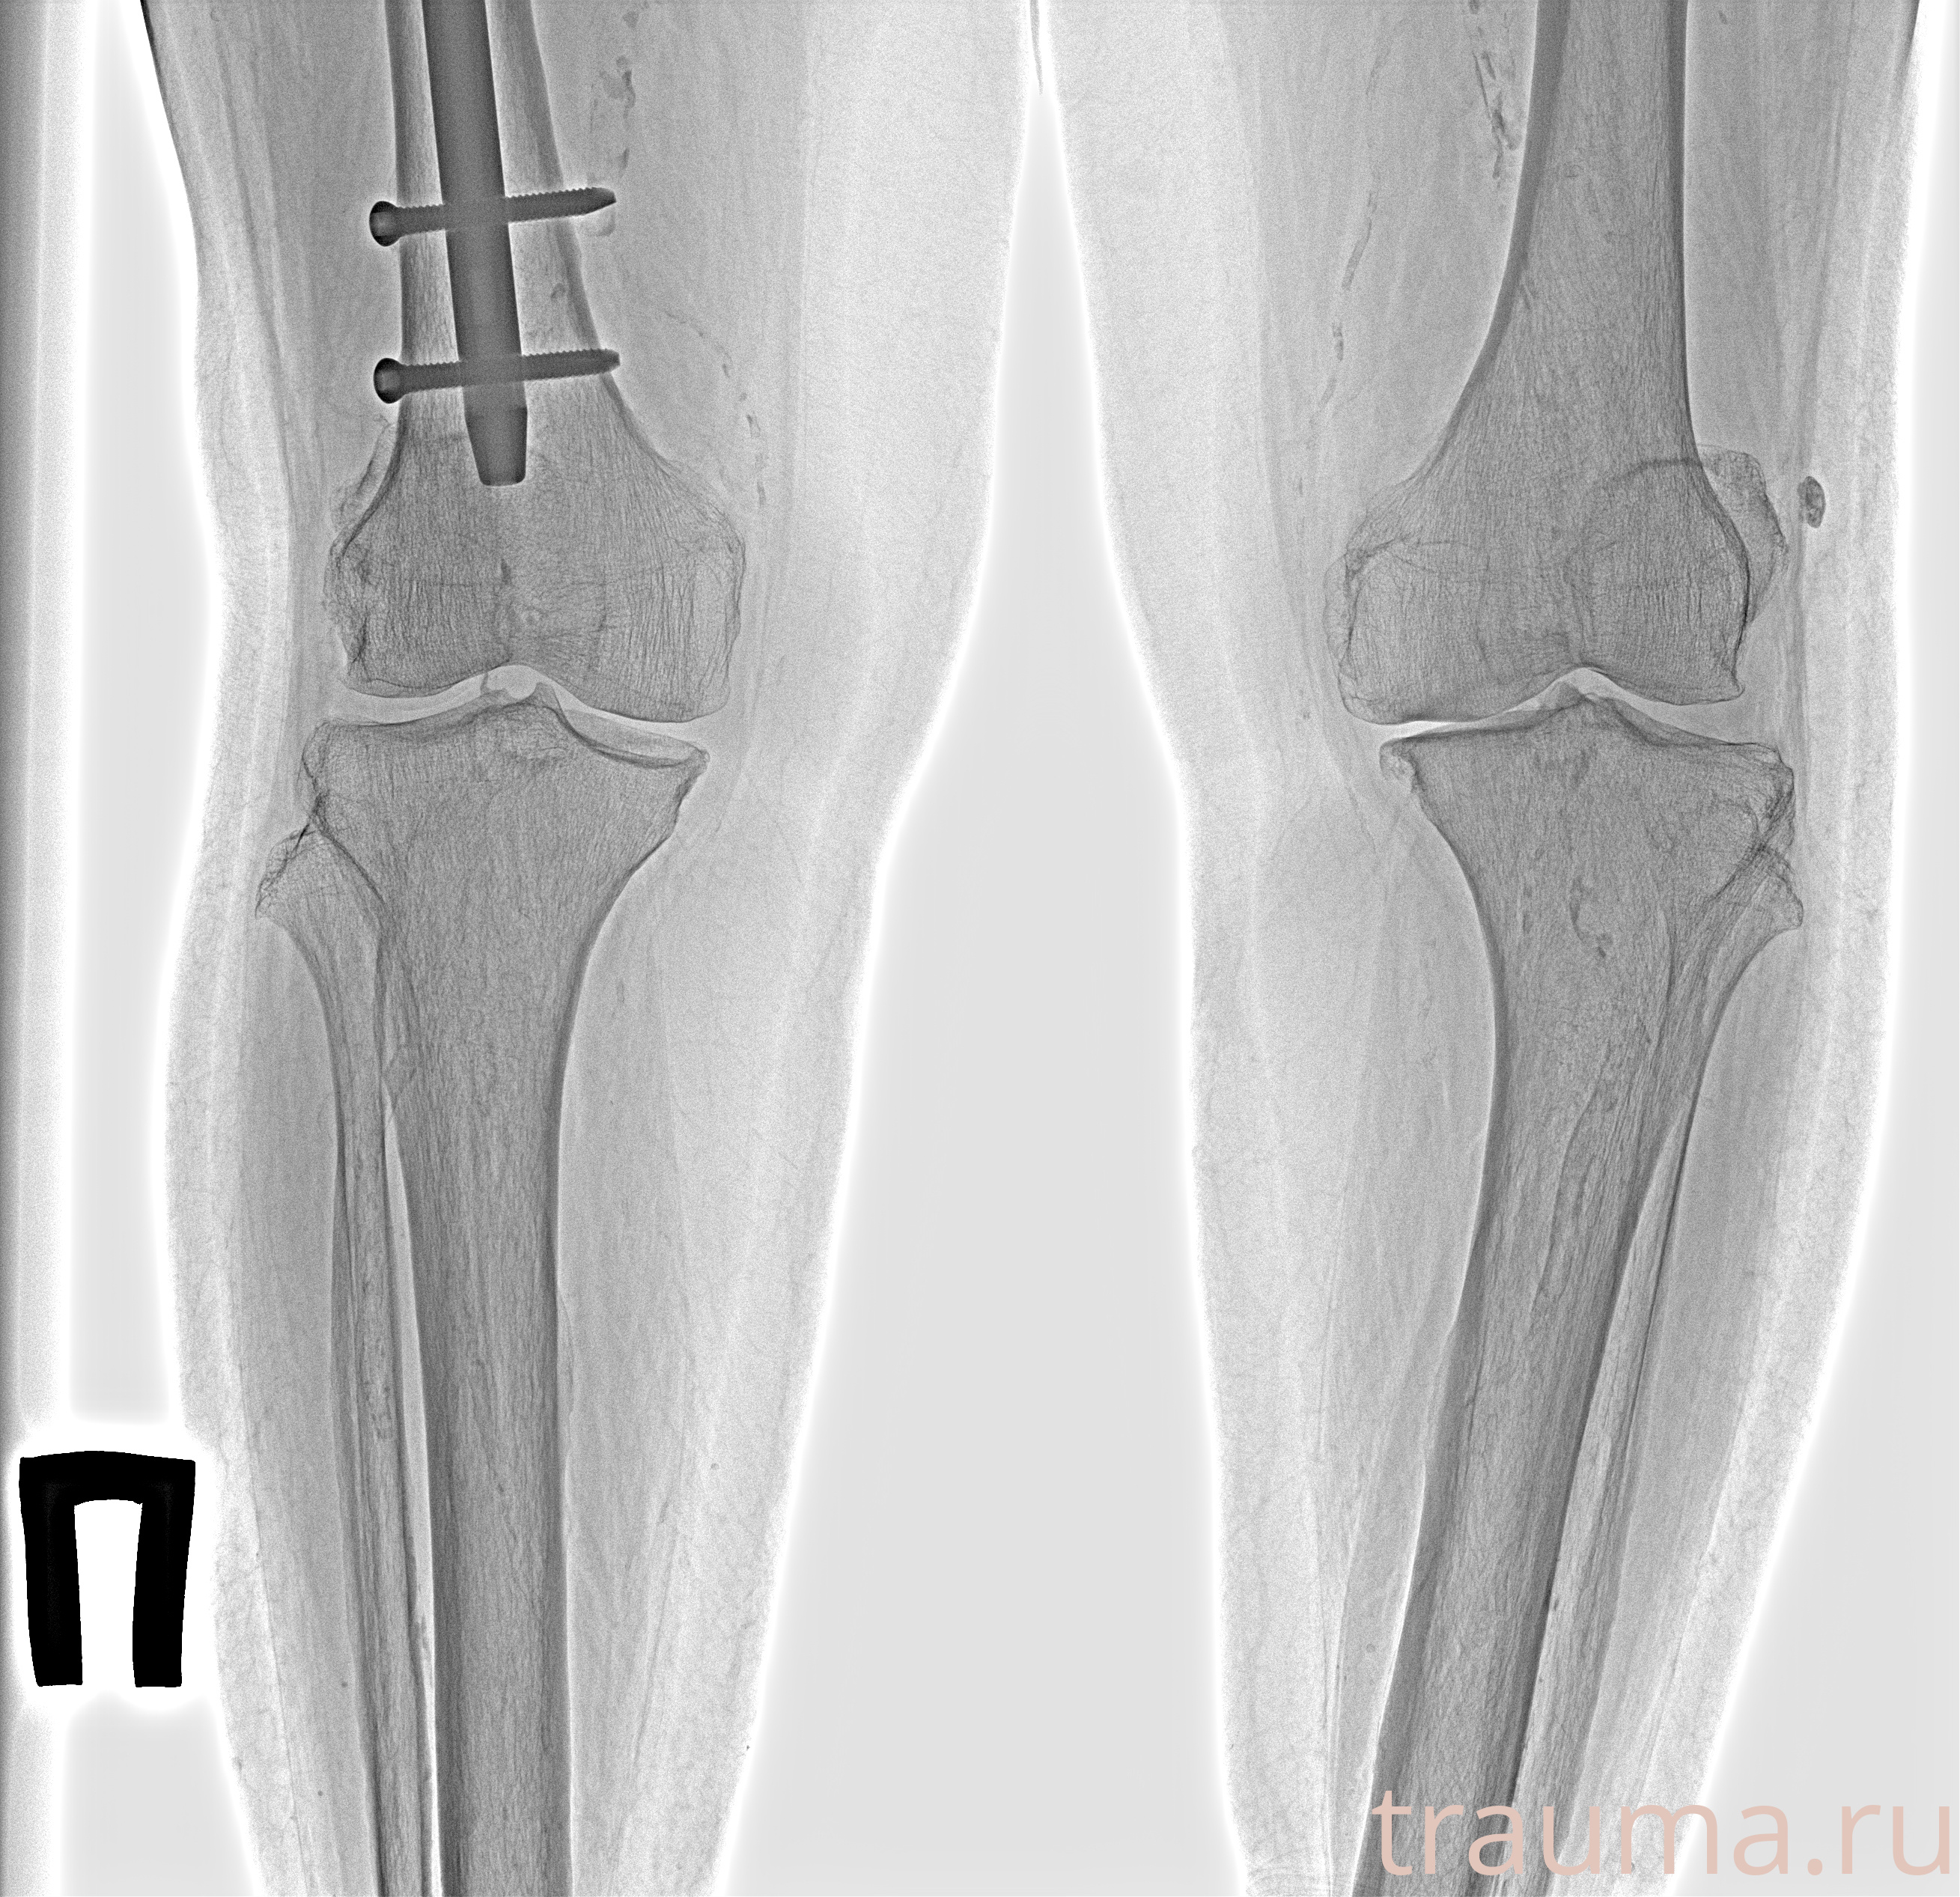

Рентгенограммы

Рентген на дому: по вашему адресу приезжает врач-рентгенолог, травматолог-ортопед с мобильным рентгеновским аппаратом, проводит диагностику травмы или заболевания, делает необходимые рентгенограммы, дает рекомендации по дальнейшему лечению. Получить качественные снимки в домашних условиях возможно благодаря уникальной методике, разработанной МосРентген Центром для института  Склифосовского